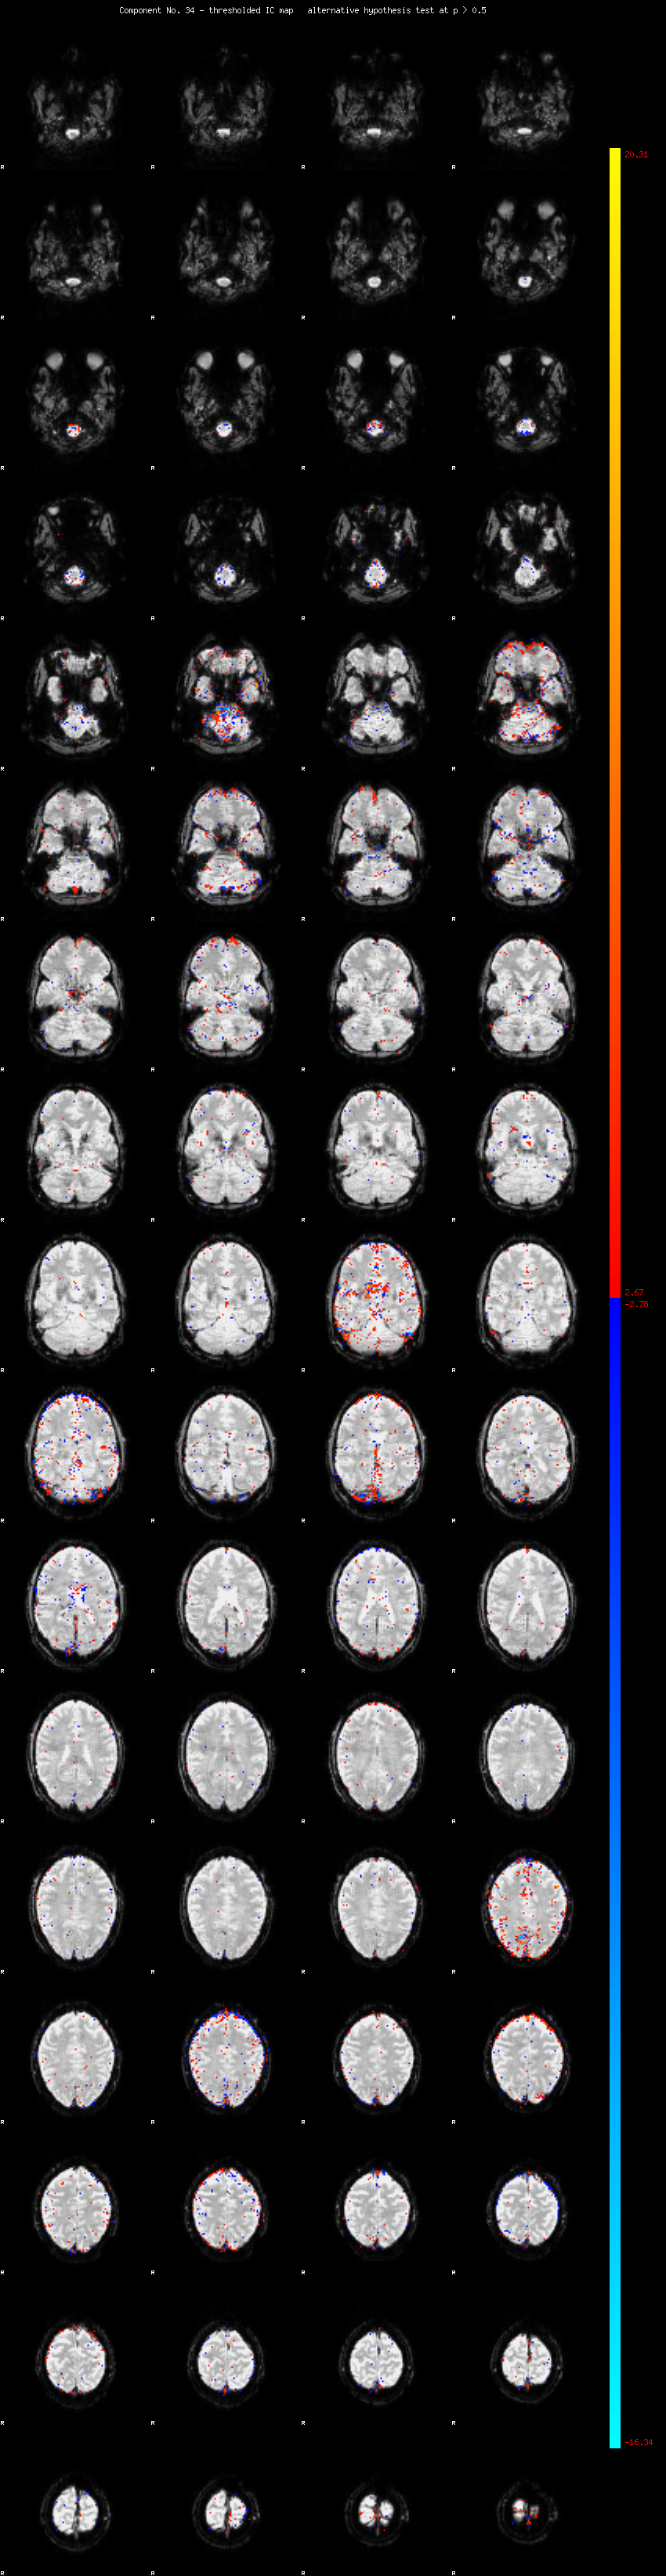

MELODIC Component 34

1.18 % of explained variance;     0.78 % of total variance